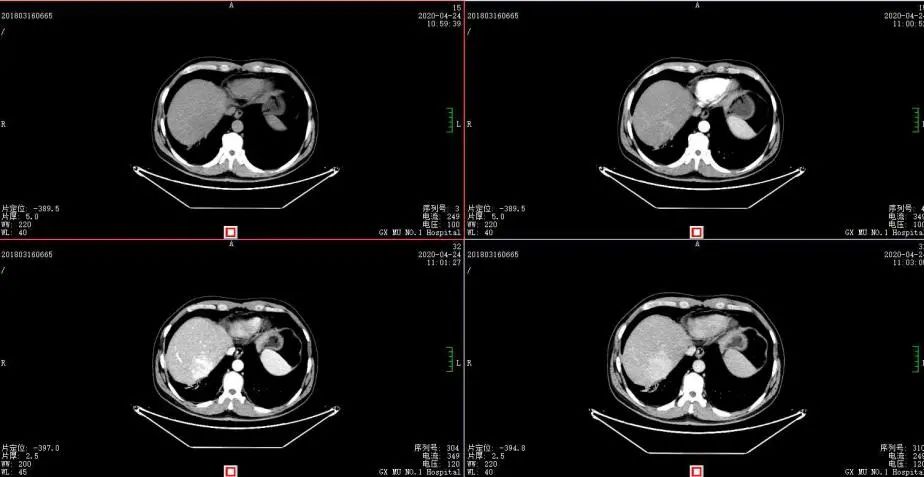

2020年4月复查:持续PR

肿瘤标志物:均正常

肝功能正常。

增强CT示:肝硬化

肝异常强化灶

考虑酒精性肝硬化可能性大,未基线使用替吉奥维持治疗。

胃癌并肝转移化疗后,肝内转移灶大致同期;

慢性肝病,脾大、门脉高压(食管下段-胃底静脉曲张);

双肾小囊肿;

右肺中叶外侧段、左肺上叶下舌段及右肺下叶后基底段慢性炎症;

右肺上叶前段实性微小结节,炎性结节?建议定期复查;

纵隔淋巴结转移瘤,复查大致同前。